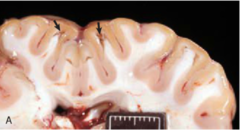

Encephalitis

Front

Inflammation of the Brain